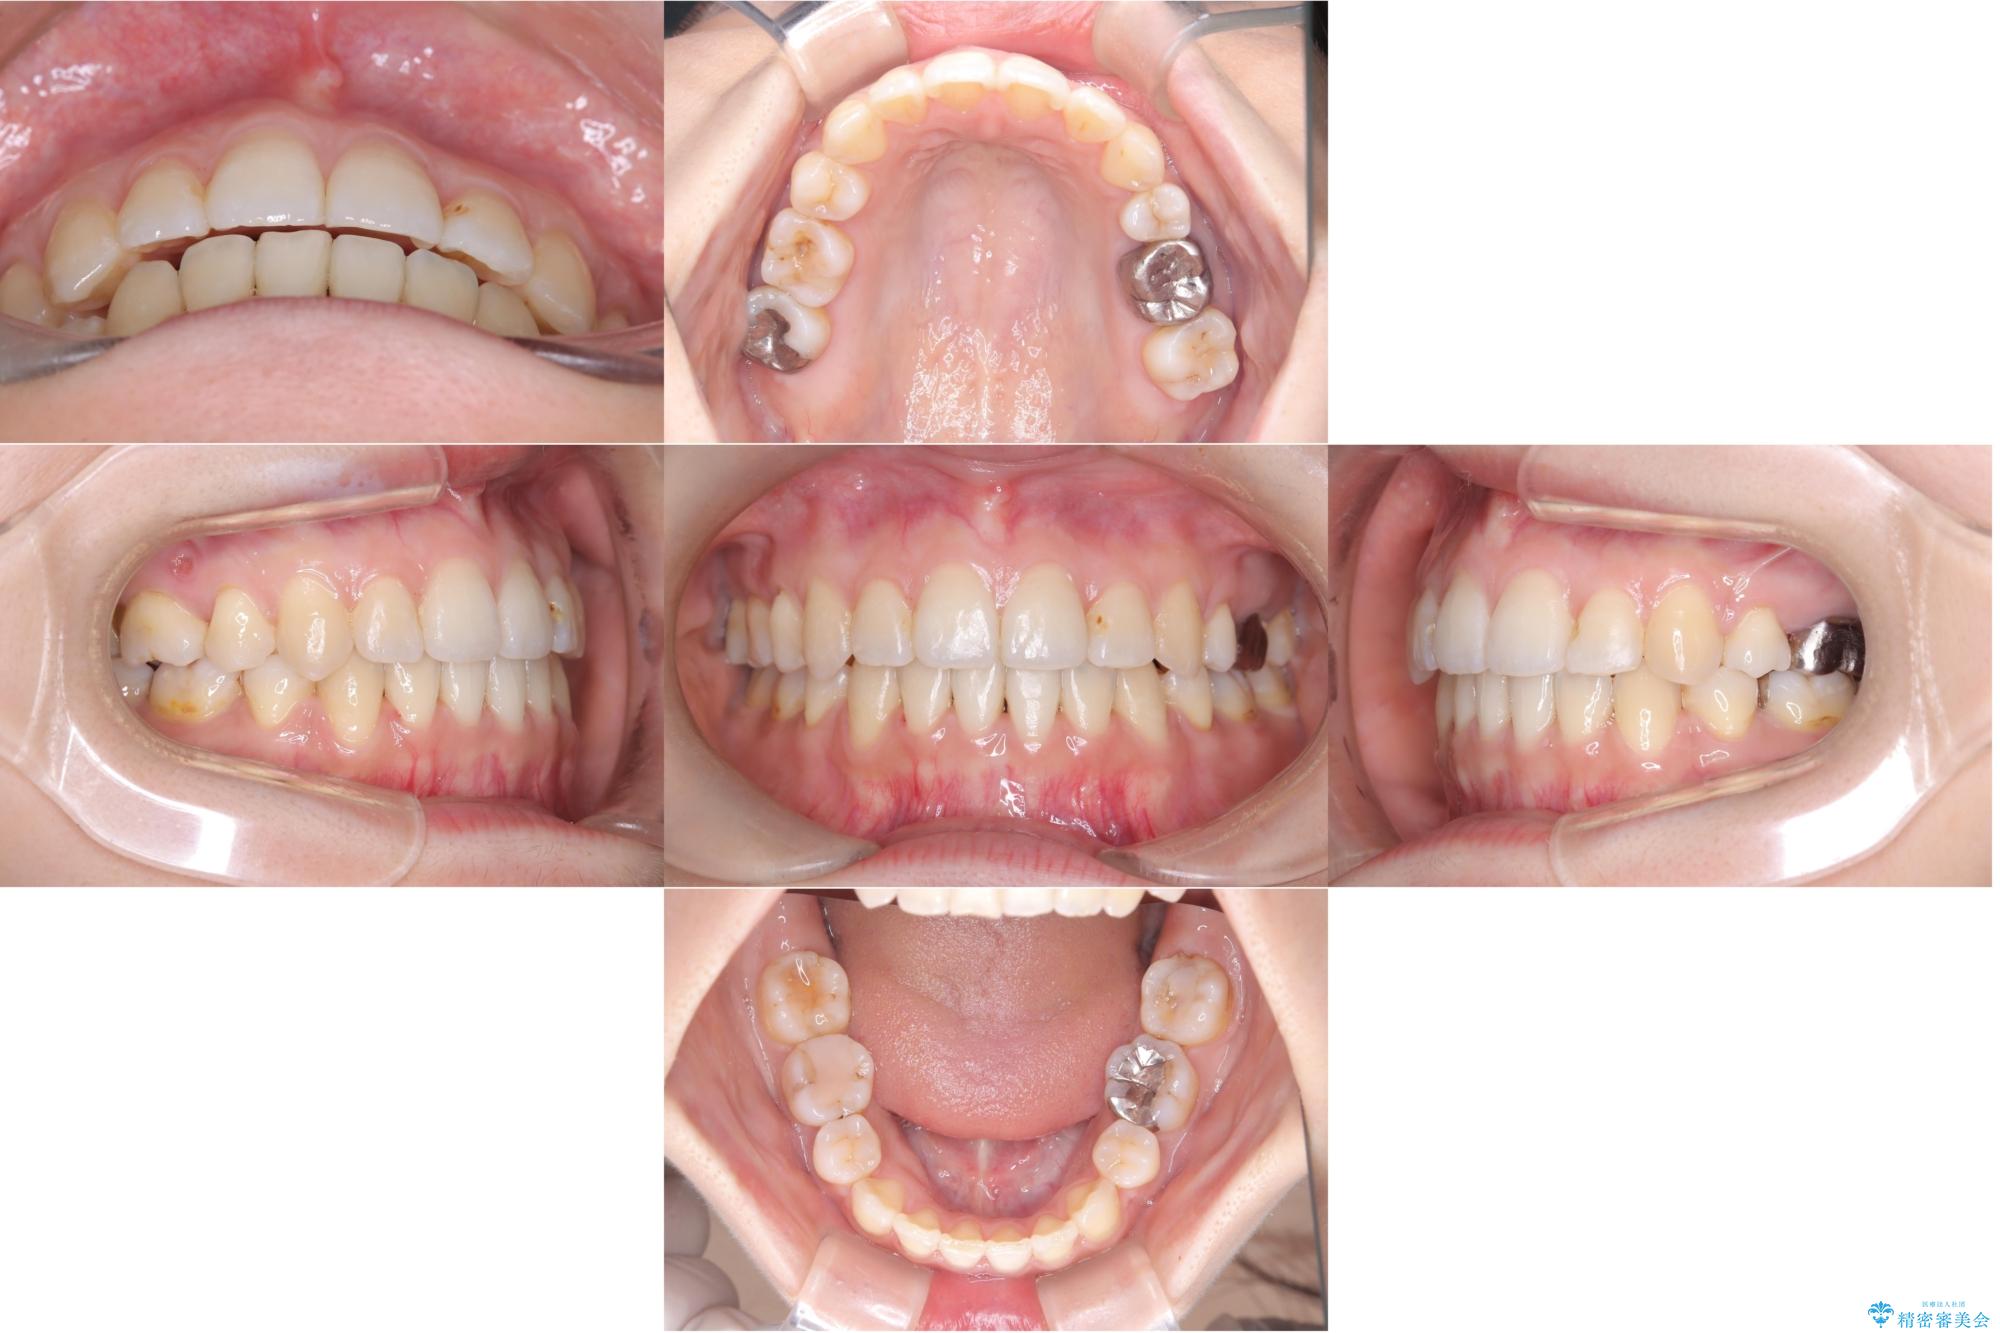

【ワイヤー矯正】口元を下げたい、下の歯の凹凸を無くしたい

- 主訴:口元を下げて前突感を無くしたい、下の歯の凹凸も無くしたい

右側第二小臼歯、左側第一小臼歯、下顎両側第一大臼歯を抜歯しワイヤ-矯正を行いました。

骨格的顎の変位を認めたため、顔貌に対しピッタリ上下の歯の正中を合わせることは難しいと説明し、上下左右計4本小臼歯を抜歯しワイヤー矯正治療を行いました。